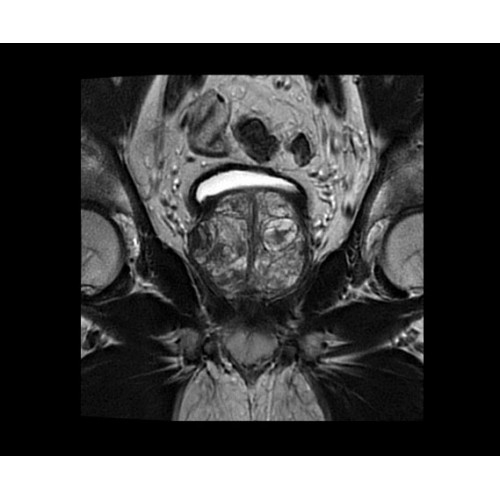

SIGNA PET/MR 3.0T — это гибридная система, в которой совмещаются две принципиально разные технологии — магнитно-резонансную томографию (МРТ) и позитронно-эмиссионную томографию (ПЭТ). Система отличающийся высокой чувствительностью и эффективностью и предназначена для диагностики в области онкологии, неврологии, кардио-васкулярных исследований, исследований воспалительных процессов.

Впечатляющие клинические возможности

Система SIGNA PET/MR предлагает впечатляющие клинические возможности и открывает доступ к наиболее полным пакетам программных приложений.

• Приложения для коррекции артефактов движения — используйте наиболее широкий набор инструментов, таких как PROPELLER, PROMO и навигаторы Pencil Beam, позволяющих снизить влияние непроизвольных или физиологических движений на качество изображений.